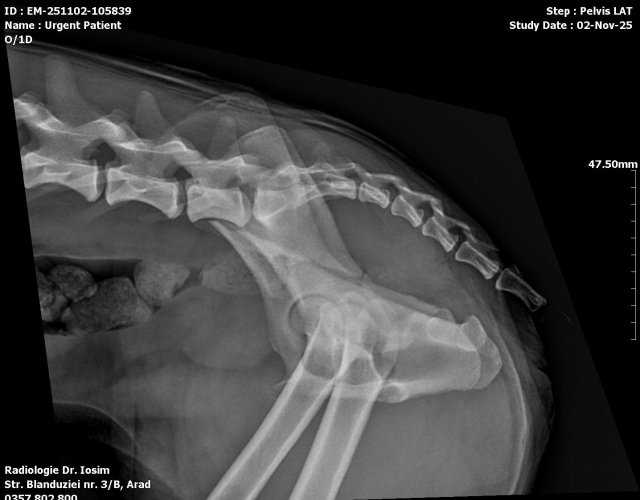

Caine accidentat

O doamna a gasit un caine lovit de masina si l-a tras pe marginea drumului pentru a suna peste tot in cautare de ajutor. Am raspuns pozitiv si am facut totul pentru el. Din pacate nu a putut fi salvat, decedand a doua zi dupa interventia chirurgicala. Foarte probabil din cauza unei embolii pulmonare. Le multumim celor care au donat. Medicul a anulat factura iar banii vor ajuta desigur alte animale de care ne ocupam zilnic.